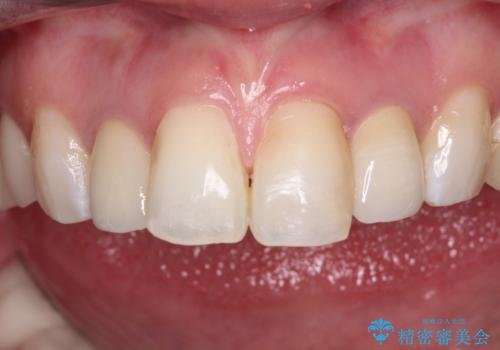

- クラウンから金属の土台が見えてきてしまったとのことで、作り替えを希望して来院された患者様です。

前歯や金属が露出している歯、痛みを感じる歯を中心に、オールセラミッククラウンにて補綴治療することとしました。

以前はセラミッククラウンのフレームとして金属が使用されており、歯肉の経年変化やセラミックのすり減りなどにより、金属が見えるようになってくることがあります。

現在は金属の代わりに強化セラミックを使用したオールセラミッククラウンが主流です。金属色が気になる方はご相談ください。